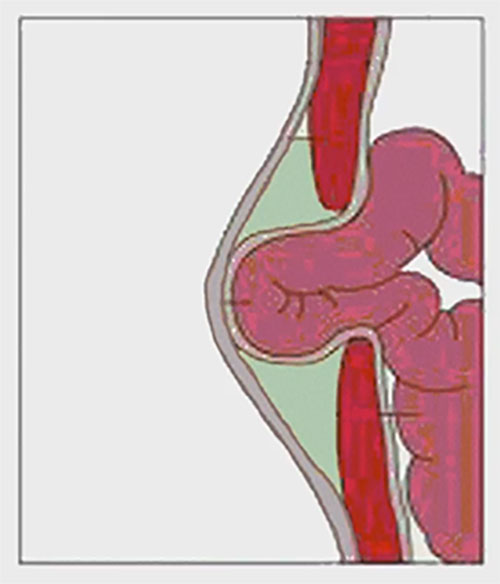

Чаще всего грыжа возникает вследствие дефекта передней брюшной стенки, слабости пупочного кольца. Провоцирующим моментом является длительное повышение внутрибрюшного давления в результате сильного кашля, запоров, продолжительного плача. Такие заболевания, как рахит, гипотрофия, снижающие тонус мышц, создают благоприятные условия для образования пупочной грыжи. Наиболее часто грыжа встречается у недоношенных детей. В пупочную грыжу обычно выпадают петли кишечника ребенка или сальника.

Самое частое объяснение того, что у ребенка может выпятиться пупок, – это грыжа. Обычно она носит врожденный характер и становится заметной на втором месяце жизни крохи. В норме после обрезания пуповины пупочное кольцо стягивается, сжимается. Если этого не происходит, или оно не закрывается до конца, формируется выпячивание. Особенно оно заметно, когда ребенок плачет или кашляет. Любое напряжение мышц живота выдает грыжу. Причем в обычном состоянии, когда малыш лежит, он спокоен, она может и не выдавать себя.

Образование врожденной грыжи. Как уже было сказано, поводом для образования грыжи является ослабление брюшной стенки. И существуют определенные причины, по которым ее формирование в утробе матери происходит не так, как это необходимо. А главной причиной слабости брюшины становится недостаточная прочность мышечной структуры и соединительных тканей — поэтому брюшина начинает развиваться с дефектами. В результате грыжевое образование возникает еще до рождения ребенка, ведь в утробе матери внутренние органы уже начинают оказывать давление на место соединения с пуповинным канатиком.

Пупочная грыжа у новорожденных может быть прямой или косой. В первом случае грыжевой мешочек и его составляющие просто выходят за пределы пупочного кольца. Во втором — возникает более сложная структура: грыжевой мешок сначала оказывается в просвете между поперечной фасцией и белой линией живота, а затем выводится в пупочное кольцо.

Грыжа у новорожденного как правило бывает «мобильной» и легко вправляемой в пупочное кольцо. Правда, и невправляемые, неподдающиеся грыжи тоже иногда встречаются, хотя и нечасто. Пупочное кольцо в норме бывает эластичным и широким, поэтому и грыжевой мешочек свободно перемещается внутрь и наружу. Если кольцо узкое, то подвижность грыжи значительно снижается.

При дополнительных факторах риска (к примеру, брюшная стенка ослаблена, пупочное кольцо недостаточно крепкое, пупок долго зарастает изнутри) часть органов выпадает из брюшины, и возникает грыжевое образование. Кстати, неграмотные действия родителей тоже могут стать причиной образования грыжи — особенно, если маме или папе не терпится поскорее посадить или поставить ребенка вертикально, помещая в прыгунки или ходунки, а его организм к этому еще не готов. В таком случае при резком увеличении давления на брюшную полость появляется грыжевое образование. Поэтому не стоит торопить события и ускорять природные процессы до того, как малыш достигнет 9-месячного возраста. Пусть ребенок развивается постепенно и поступенчато: сначала он начнет самостоятельно сидеть, затем — ползать и только потом встанет на ноги. Предварительные стадии существуют не просто так — они задуманы природой для укрепления брюшных мышц, которые готовятся к тому, чтобы спокойно выдержать давление внутренних органов без образования грыжи.